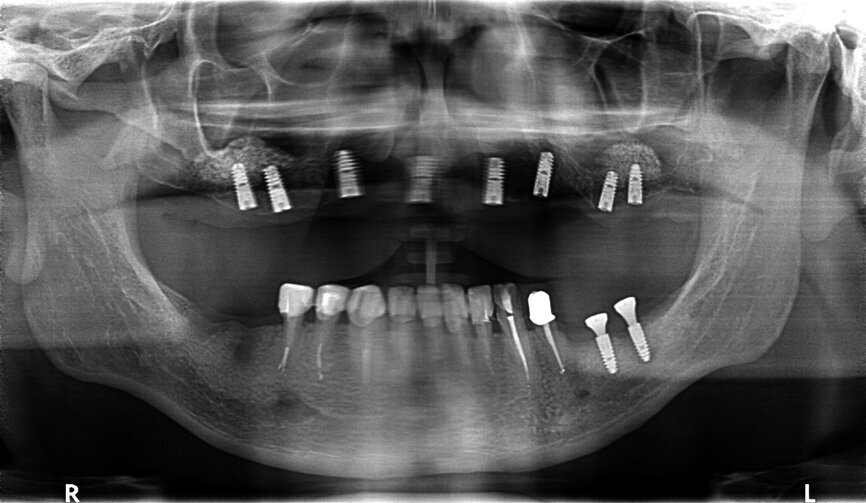

Fig. 30: OPG after placing implants.

Fig. 31: OPG after exposing implants at the lateral section and having used a temporary prosthesis based on telescopes.

Fig. 32: OPG after treatment.

If the quality of the work satisfies our expectations, we may proceed to the handing-over stage and perform the functional and aesthetic analysis, both intra- and extraorally. A perfect conclusion to the treatment process is the receipt of a complete set of OPG X-rays taken before, during and following treatment (Figs. 29–32).